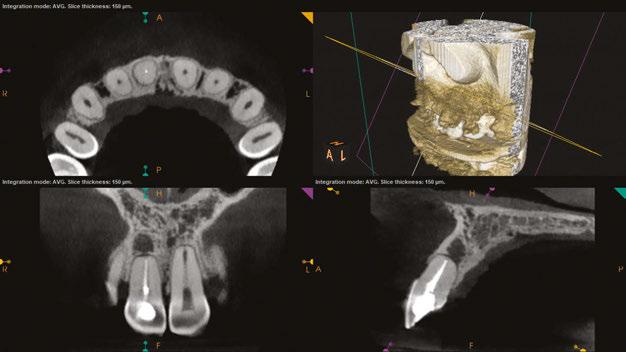

USA, Savannah, Georgia) and gutta percha via continuous wave condensation. EndoSequence BC liner blue (Brasseler USA, Savannah, Georgia) was placed over the gutta percha at the canal orifice, and the tooth was temporized using a cotton pellet and Fuji IX placed in the access (Figure 6). Following completion of the root canal, the patient was scheduled for a 3-month reevaluation and referred to her provider for definitive restoration. Healing was observed at the 3- and 6-month postoperative visits. Periapical radiographs were exposed at each visit revealing bony healing (Figure 7). The patient reported no pain or symptoms following nonsurgical root canal treatment. At both visits, percussion and palpation were negative. A CBCT was captured at the 6-month postoperative exam to evaluate healing. Coronal CBCT slices revealed a reduction in lesion size to 3.5 mm x 1.6 mm. Sagittal slices also showed reduction in lesion and maintained health of bone surrounding implant No. 12 (Figure 8). A 2011 article by Ng outlines eleven factors that, if present, improve periapical healing following primary non-surgical root canal treatment.17 Only two of these eleven factors, absence of a preoperative periapical lesion and size of the preoperative periapical lesion, were not met in this case report. Along with this and the 2017 AAE Treatment Options for the Compromised Tooth: A Decision Guide article, the final prognosis for healing is favorable.16

Figures 8A-8B: CBCT was taken at the 6-month postoperative visit. 8A. Coronal CBCT slices revealed a reduction in lesion size to 3.5 mm x 1.6 mm. 8B. Sagittal CBCT slices revealed a reduction in lesion size and maintained health of bone surrounding implant No. 12